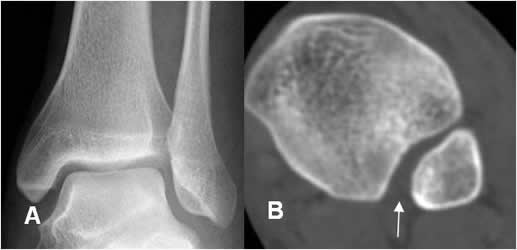

Fig 89. Lesión de ligamentos de la mortaja tibioperonea.

A: Rx AP. Aumento del espacio tibioperoneo y disminución de la sombra tibioperonea, lo que hace sospechar lesión ligamentaria.

B: TAC axial. Aumento del espacio tibioperoneo posterior, por lesión ligamentaria.